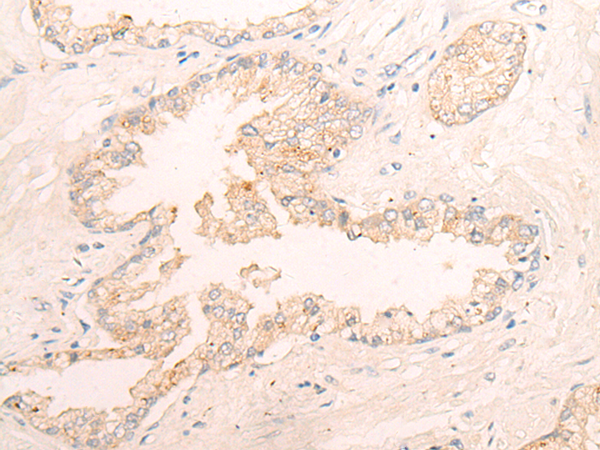

IHC positive control: |

Human thyroid cancer and Human prostate cancer |

IHC Recommend dilution: |

30-150 |